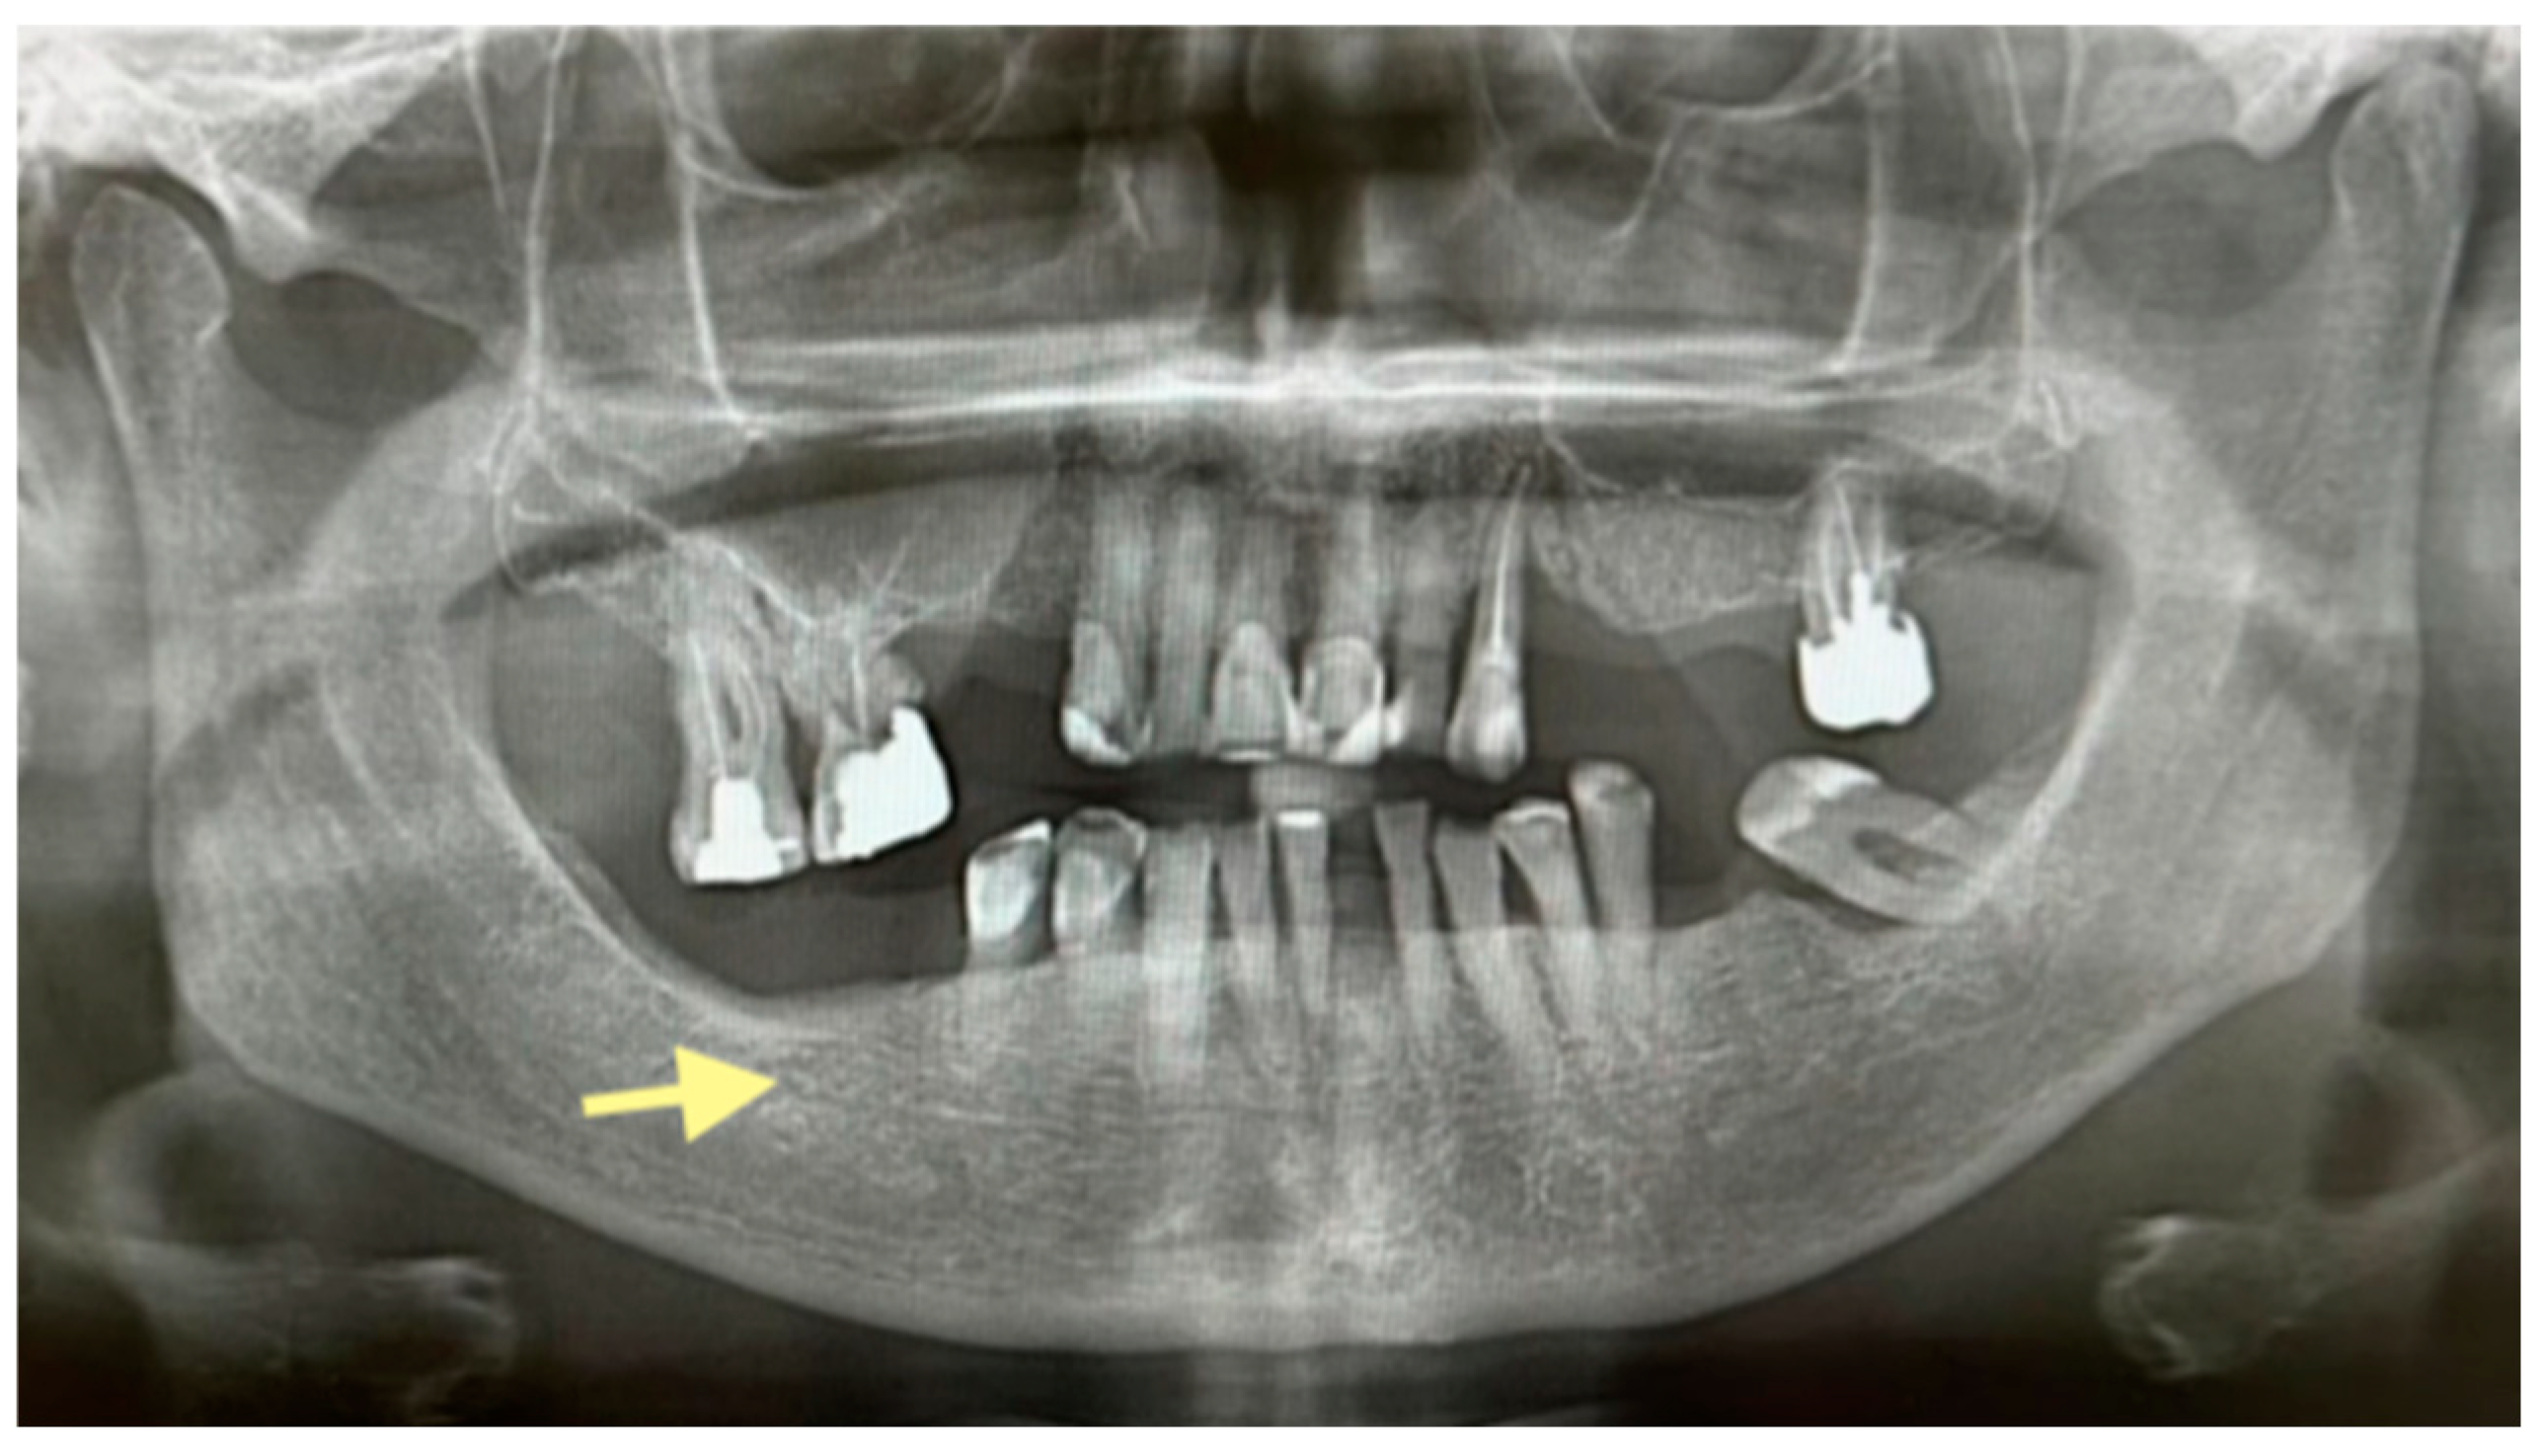

Figure 4.

OPG (orthopantomogram) before surgery (12 January 2024). In the fourth quadrant, we do not see any changes, which are typical in the initial stages of osteonecrosis.

Figure 5.

OPG (orthopantomogram) performed on 21.08.2024.